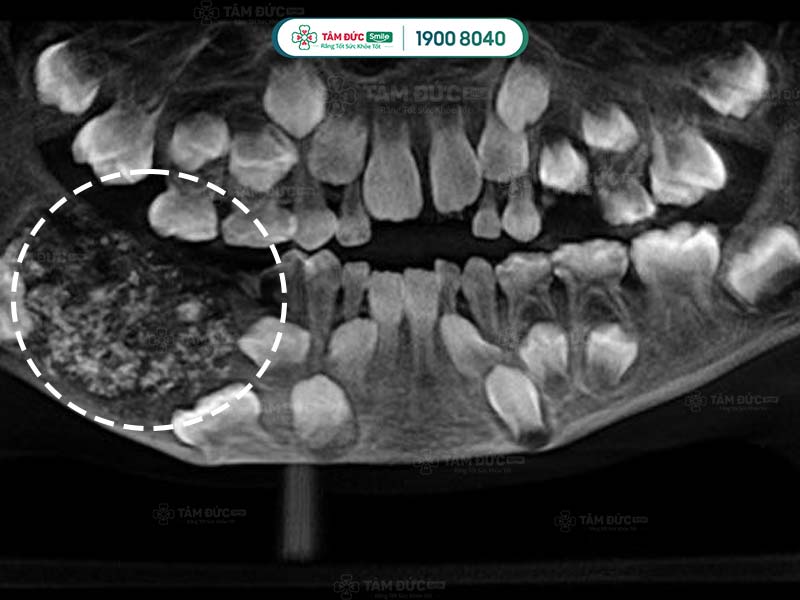

5.2. Chụp CT scan cho u răng

Sử dụng phương pháp chụp CT Scan để nhìn thấy rõ được cấu trúc bên trong khối u răng đó như thế nào.

Trong một số trường hợp cần thiết như u răng phức hợp phát triển vào khoang mũi. Cần thực hiện thêm 1 số xét nghiệm khác như chụp cộng hưởng từ MRI… Để có thể đưa ra được phương pháp điều trị phù hợp.

1.2. U răng phức hợp

- Thường xuất hiện ở vị trí hàm răng dưới.

- U răng phức hợp giống như một khu vực cản quang với các mật độ u khác nhau ở từng dạng bệnh.